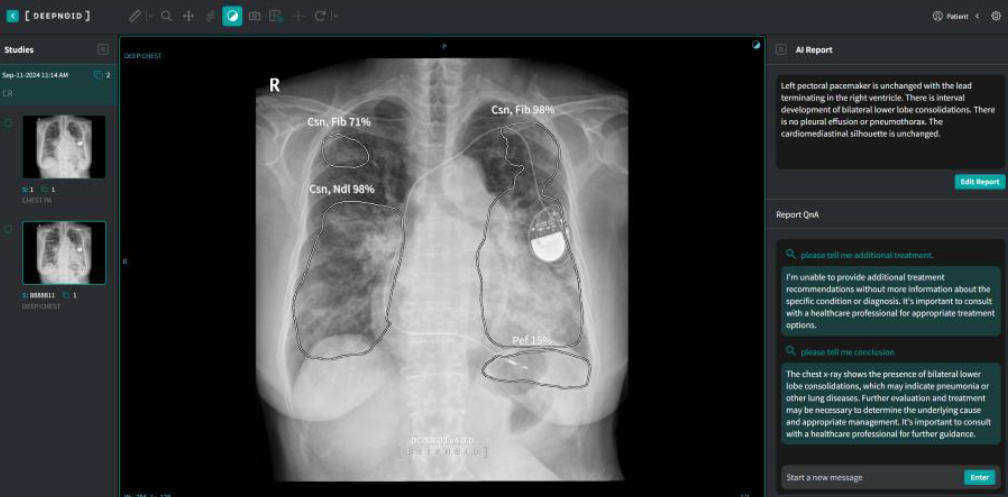

딥노이드의 M4CXR은 흉부 X-레이 영상을 분석해 판독문 초안을 생성하는 거대 언어 모델(LLM)로 설계된 클라우드 기반의 의료 AI 솔루션이다. 연구를 통해 M4CXR은 흉부 X-레이 진단 시 실제 의료현장에서 임상의의 역량을 강화하는 보조 도구로 적합함을 입증했다.

이번 연구는 의료 AI 관련 전문가인 인하대병원 영상의학과 이로운 교수의 주도로 진행했다. M4CXR과 챗GPT의 판독 결과를 ▲정확도 ▲위양성 ▲위치 오류 ▲개수 오류 ▲환각 등 다섯 개 지표로 평가했다. M4CXR은 모든 평가 항목에서 챗GPT보다 일관되게 우수한 성능을 보였다. 위치 정확성(76~77.5%)에서 챗GPT(36~36.5%)를 크게 앞섰다. 진단 정확성 측면에서도 M4CXR(60~62%)은 ChatGPT(42~45%)보다 월등히 우수했다.

연구 결과 M4CXR은 전문 의료 환경에서 활용하기에 적합했으며, 범용 AI인 챗GPT에 비해 월등히 우수한 성능을 나타냈다. 향후 M4CXR이 실제 의료 현장에서 사용될 경우, 진단 워크플로우를 최적화하고 의료 전문가의 역량을 보완할 것으로 기대하고 있다.